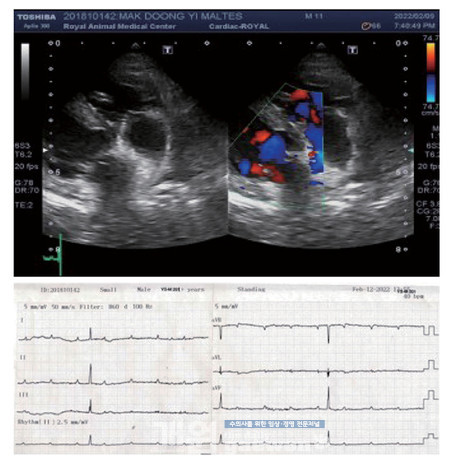

Echocardiography

심방과 심실의 수축의 miss matching 소견이 관찰됩니다. 심방 3회 수축당 심실 1회 수술이 관찰됩니다. II 유도에서 PPPQRS로 보이는 소견이 보였습니다.